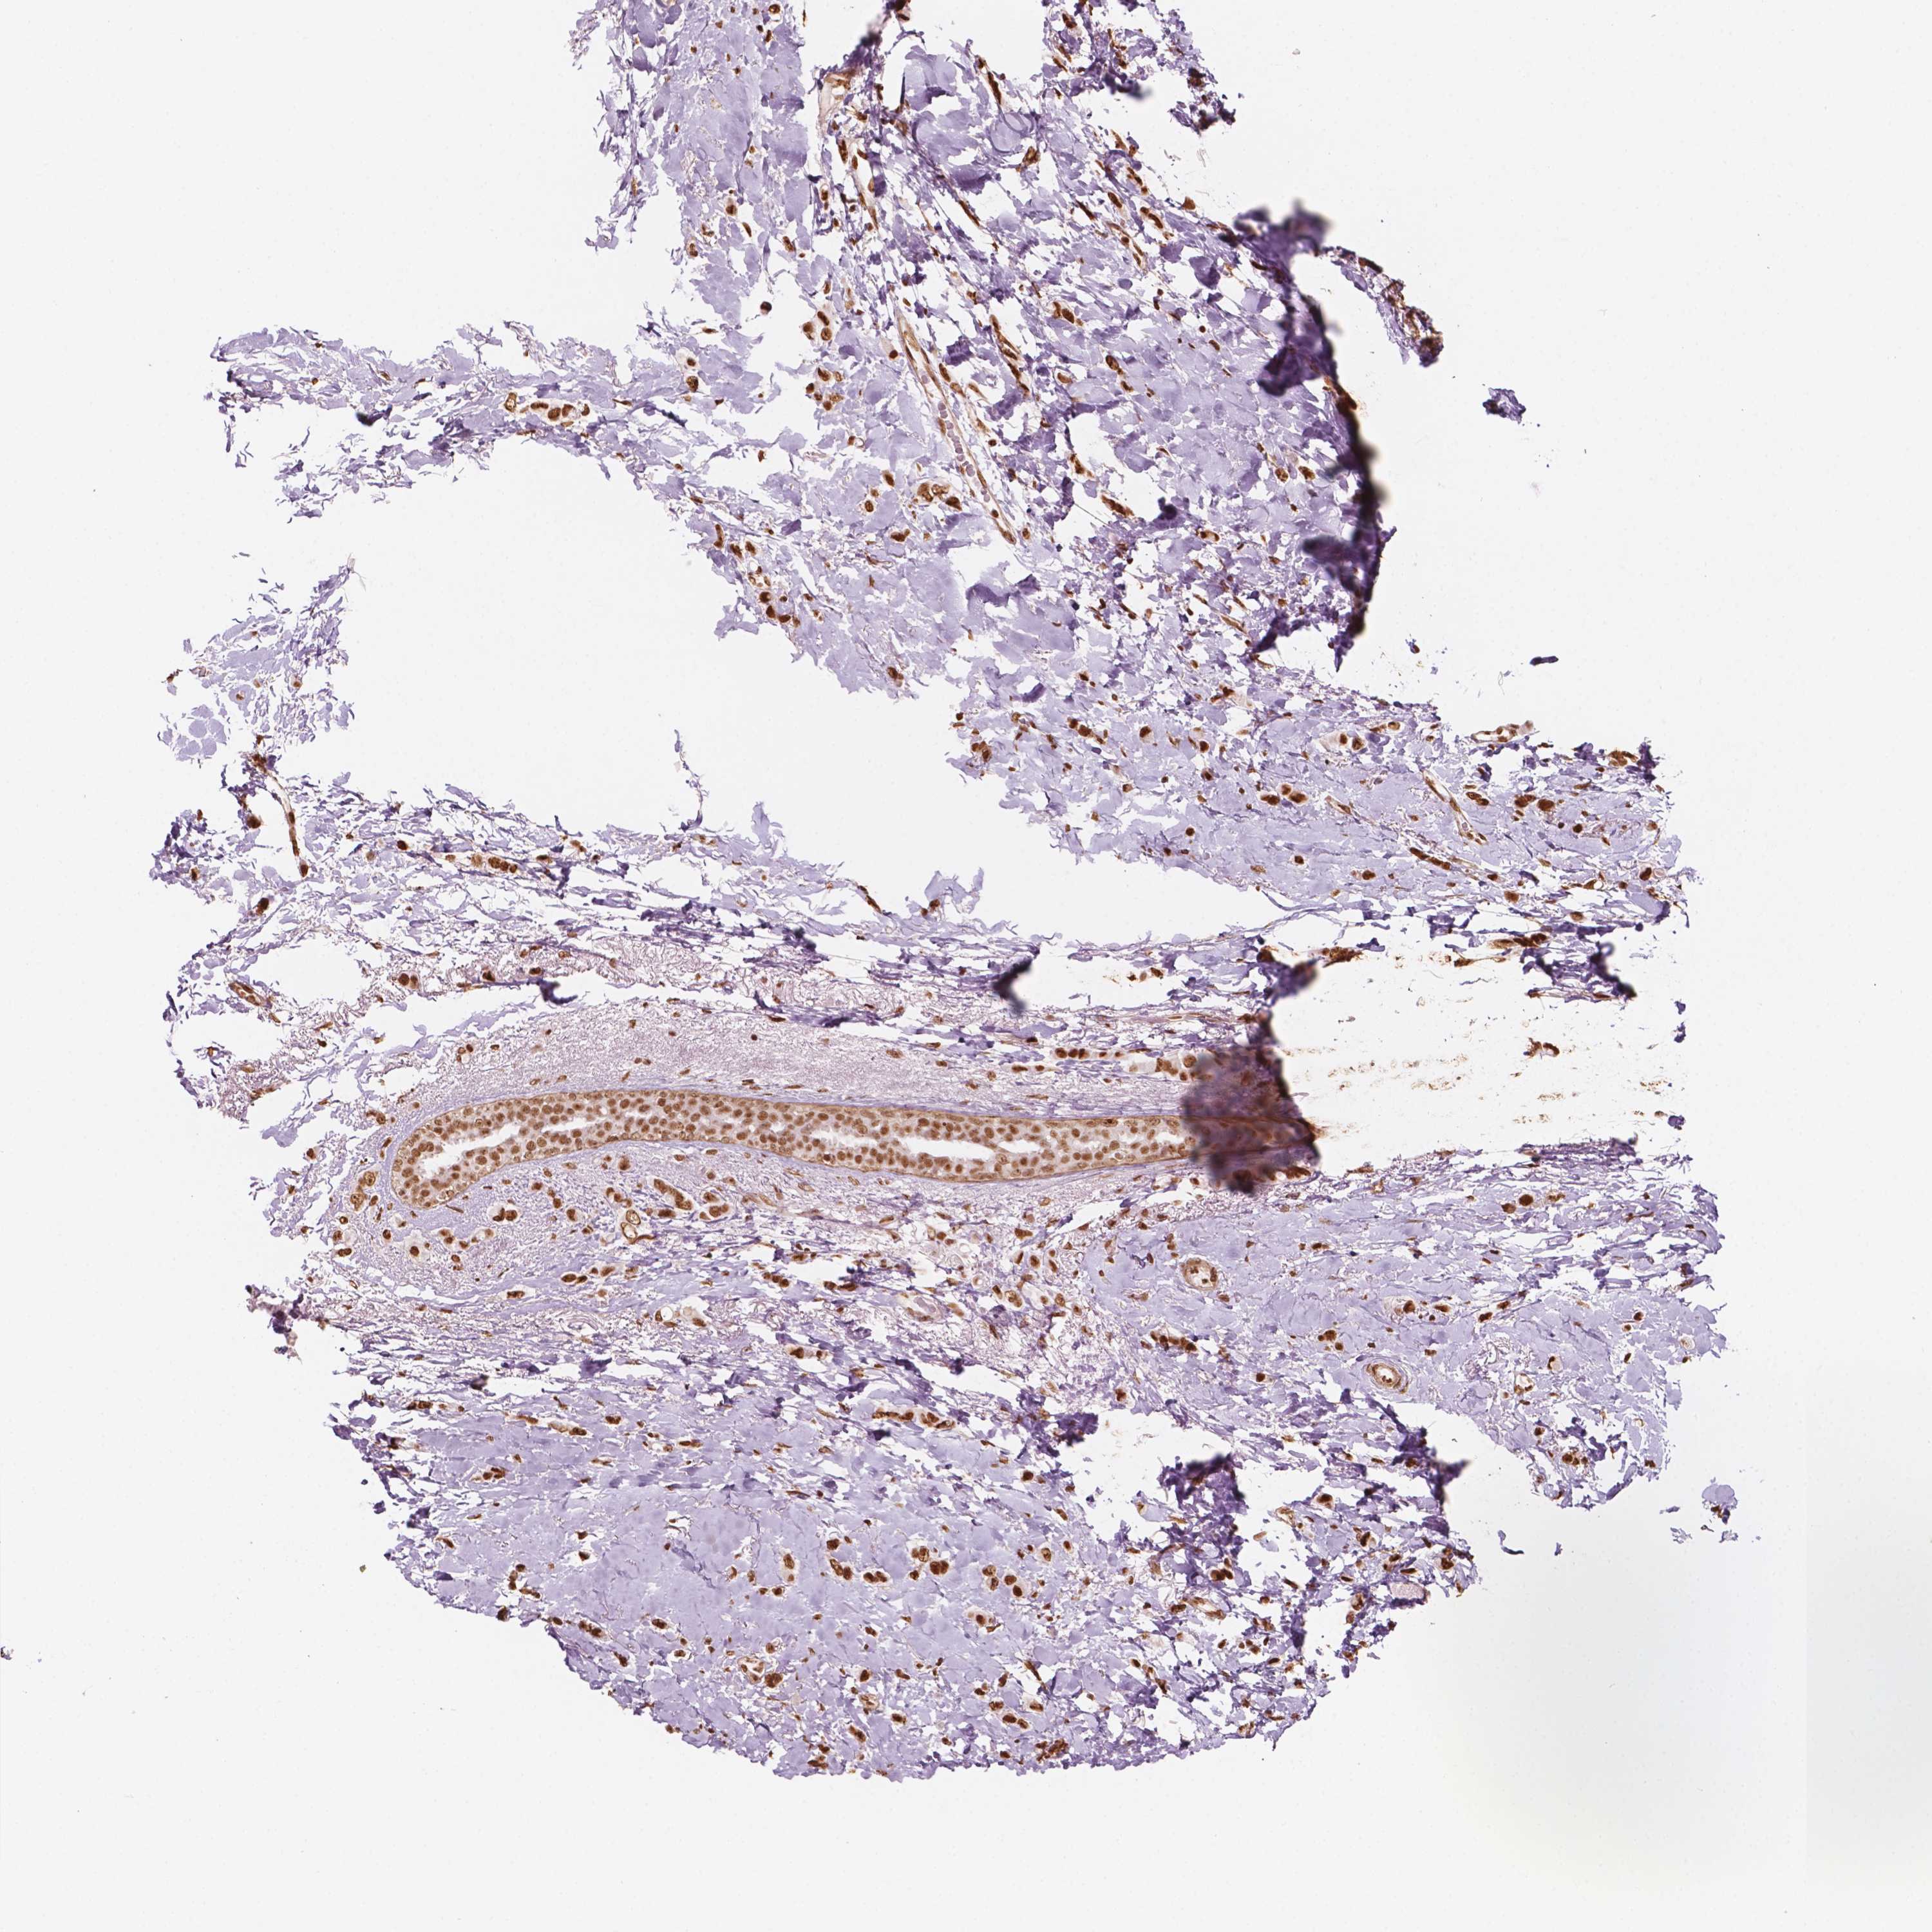

CANCER BREAST CANCER Show tissue menu

BRCA TCGA BRCA VALIDATION PROTEIN EXPRESSION